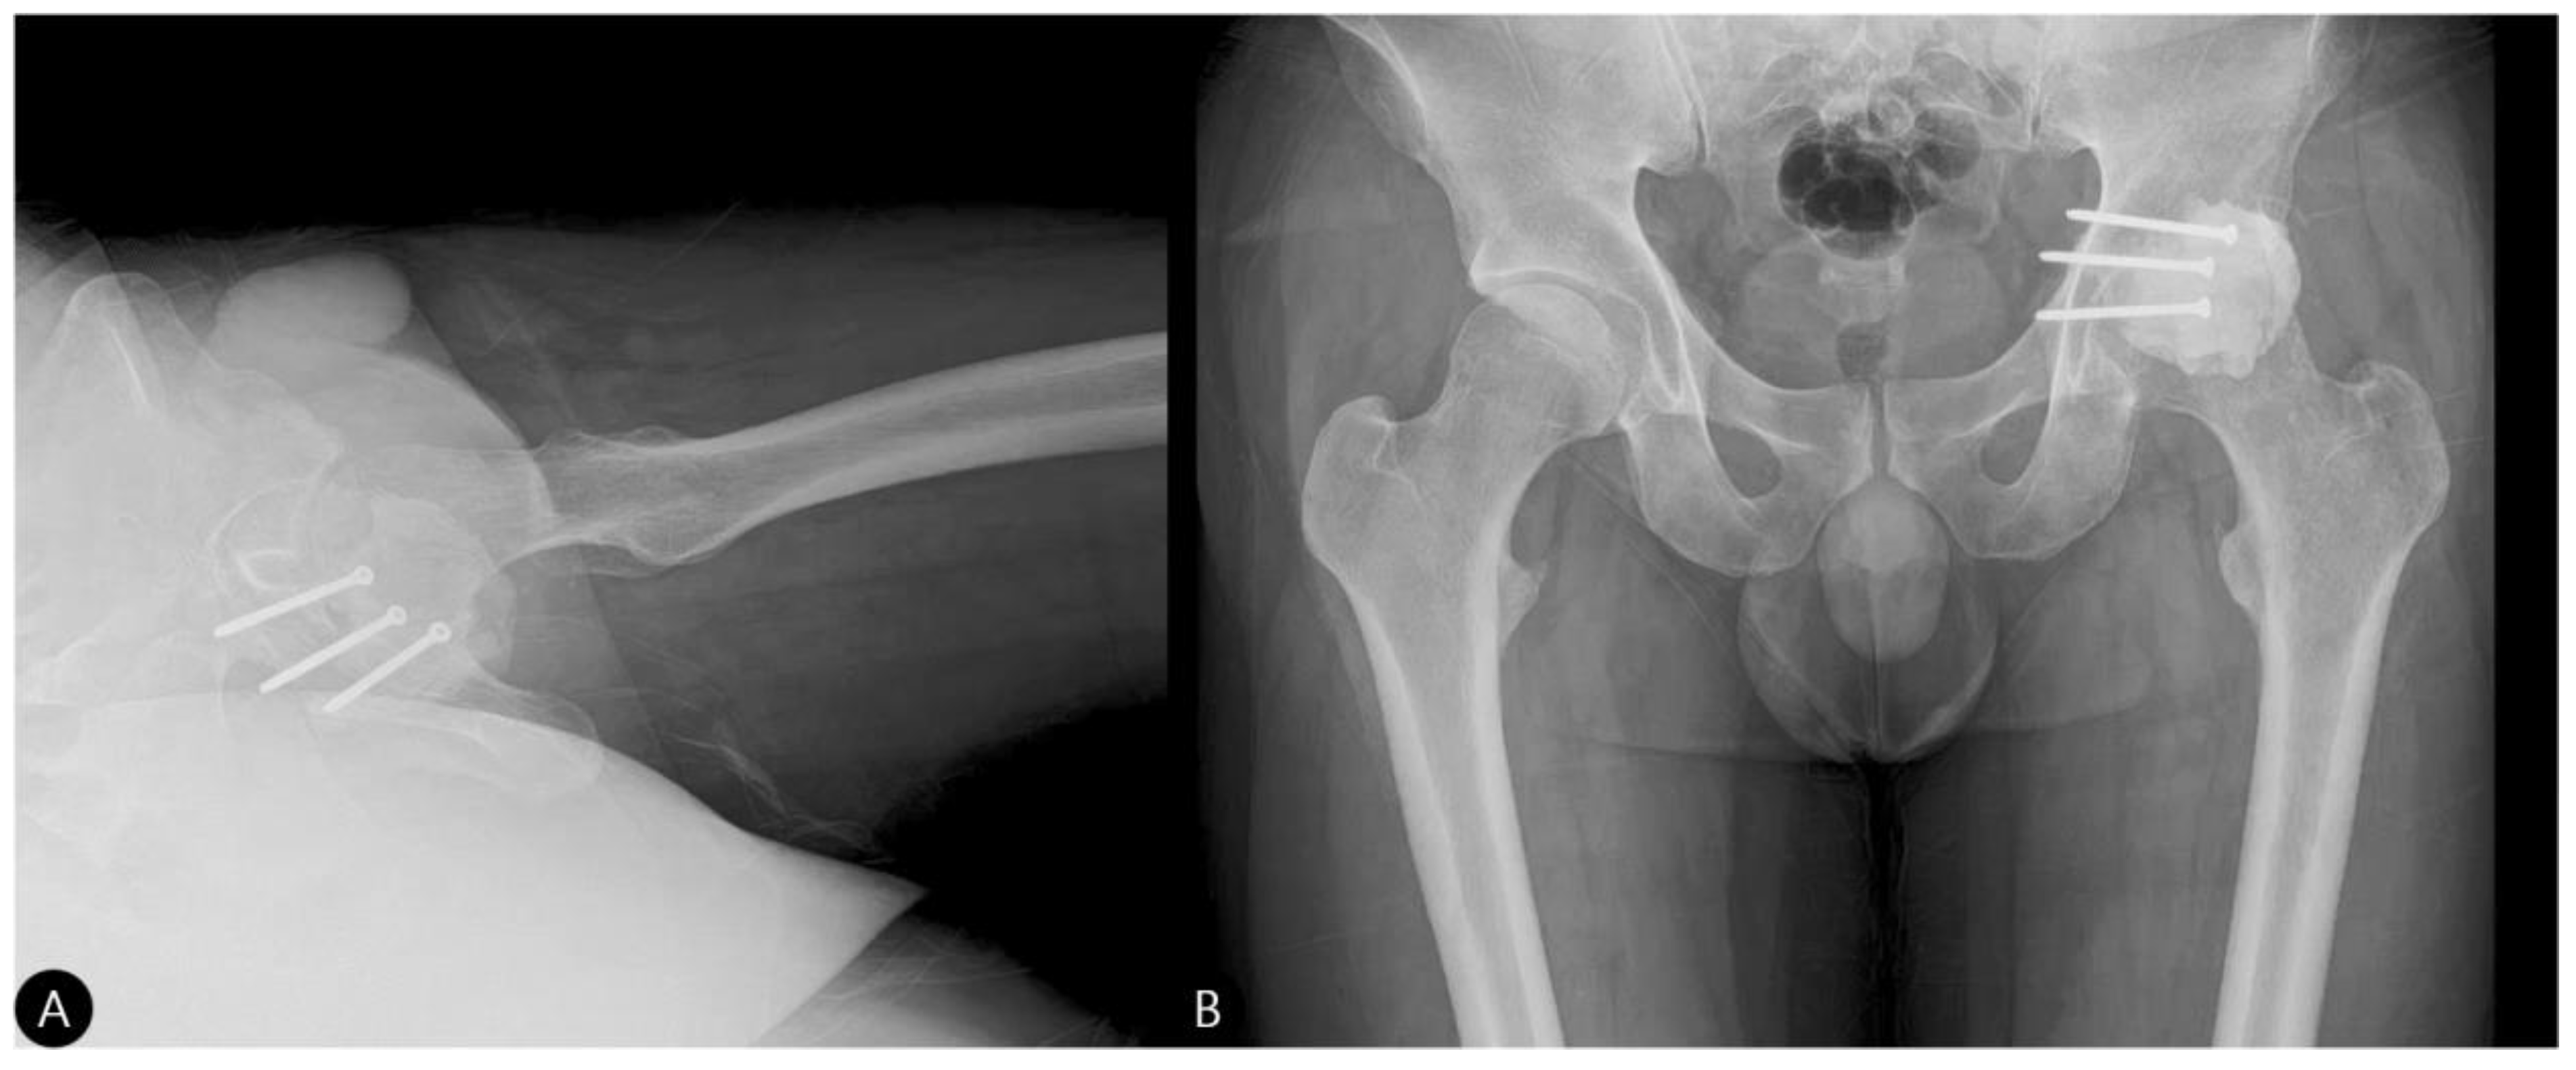

- Reduction and Final Assessment: The hip was reduced under direct vision. Intraoperative fluoroscopy confirmed a concentric reduction, correct implant placement, and the absence of cement fragments in the joint. The stability of the construct was tested through a range of motion. Postoperative imaging confirmed the anatomical reduction and the accurate contouring of the cement construct (Figure 4 and Figure 5).